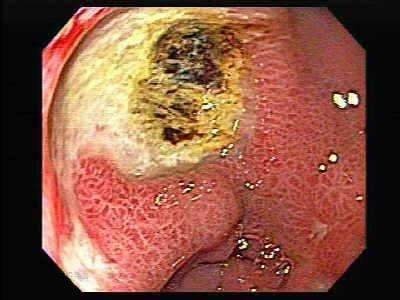

俗话说胃病“三分治七分养”,七分养应该在三分治的基础上进行。胃癌的“治”强调的是定期的体检,治“未癌”,或者是早期癌治疗。我们国家在2012年启动的早期癌症筛查计划,通过定期胃镜检查,明确到底是否存在胃的器质性病变,如浅表性胃炎、慢性萎缩性胃炎、胃溃疡、胃息肉、增生、化生等,制定治疗和随访的计划,将“蠢蠢欲动”坏细胞消灭在萌芽状态。